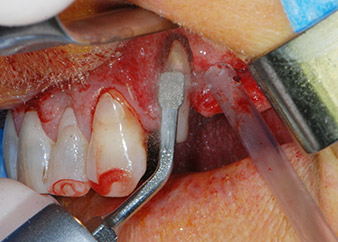

Un mese più tardi, nel giorno programmato per l'intervento, il dolore e l'infiammazione in corrispondenza del dente 24 erano minimi, ma era ancora presente mobilità di classe 2 secondo Miller. Dopo l'apertura dei lembi e la pulizia del tessuto periapicale e periradicolare infetto, l'estensione della mancanza ossea si è resa evidente (Figg. 2 e 3).

Tutto il tessuto osseo vestibolare e distale era mancante in corrispondenza della radice buccale. La possibilità di attacco era essenzialmente ristretta alla radice palatale, evidenziando la prognosi negativa preliminare. Anche il dente 27 mostrava un punto di attacco orizzontale ridotto e una rarefazione apicale minima (cfr. Fig. 1), senza sintomi clinici.

Si è mantenuta , tuttavia, l'idea iniziale di conservare entrambi i denti come appoggi temporanei del ponte durante il periodo di sei mesi per l'osteointegrazione degli impianti. In seguito la situazione si sarebbe assestata. In primo luogo, in un tentativo di risolvere il problema entro-periodontale, la superficie radicolare rimanente è stata attentamente sbrigliata con apparecchiatura piezoelettrica (Piezomed di W&H con l'attacco S1 a spatola, progettato in origine per l'erosione della parete laterale del seno mascellare) Fig. 4).